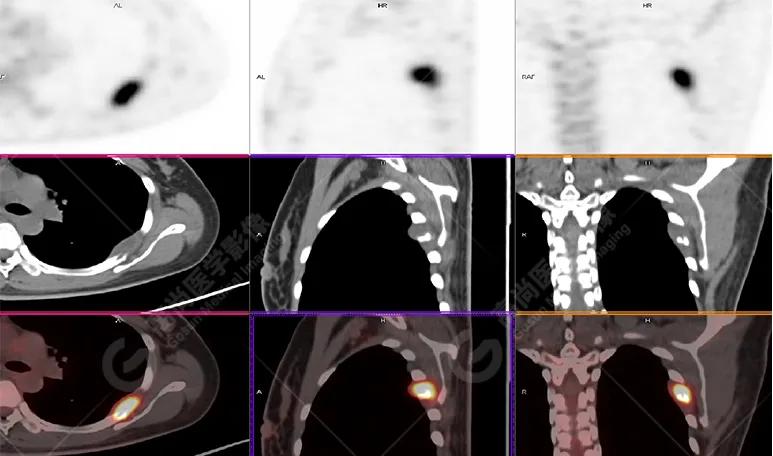

影像图

胸椎溶骨性骨质破坏,FDG环状代谢增高,SUVmax为4.0。

左侧乳腺一软组织结节,FDG代谢增高,SUVmax为2.6。

最终诊断: 左侧乳腺癌伴胸椎单发骨转移。